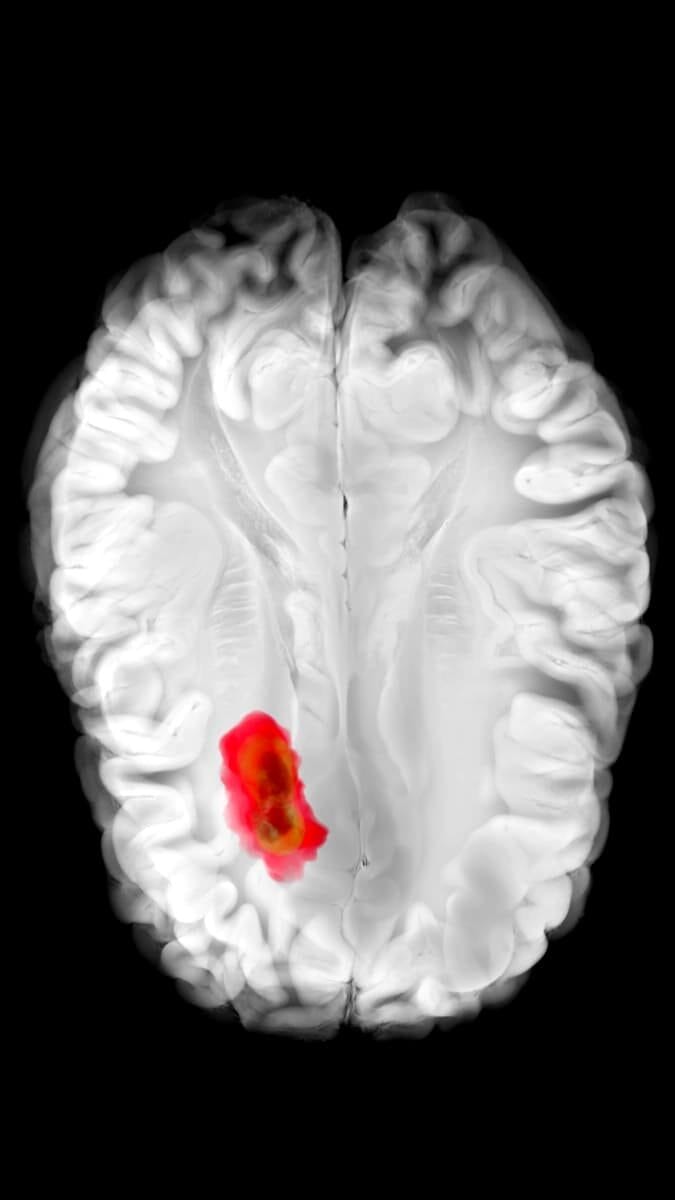

Гліобластома — це одна з найнебезпечніших форм пухлин головного мозку, яка вражає гліальні клітини. Вона характеризується стрімким ростом, високою здатністю до інфільтрації тканин і стійкістю до терапії. Навіть після хірургічного втручання, променевої або хіміотерапії пухлина часто повертається. Середній термін виживаності після встановлення діагнозу становить приблизно 12–15 місяців, попри інтенсивне лікування.

Один із механізмів, який допомагає гліобластомі виживати й поширюватися, — це активація певного метаболічного шляху, пов’язаного з ферментом 2-аміноетантіолдіоксигеназа (ADO). Цей фермент сприяє утворенню гіпотаурину — сполуки, що підтримує життєздатність пухлинних клітин та їхню стійкість до кисневого голодування й стресу. Раніше не існувало затверджених ліків, здатних пригнічувати дію ADO.